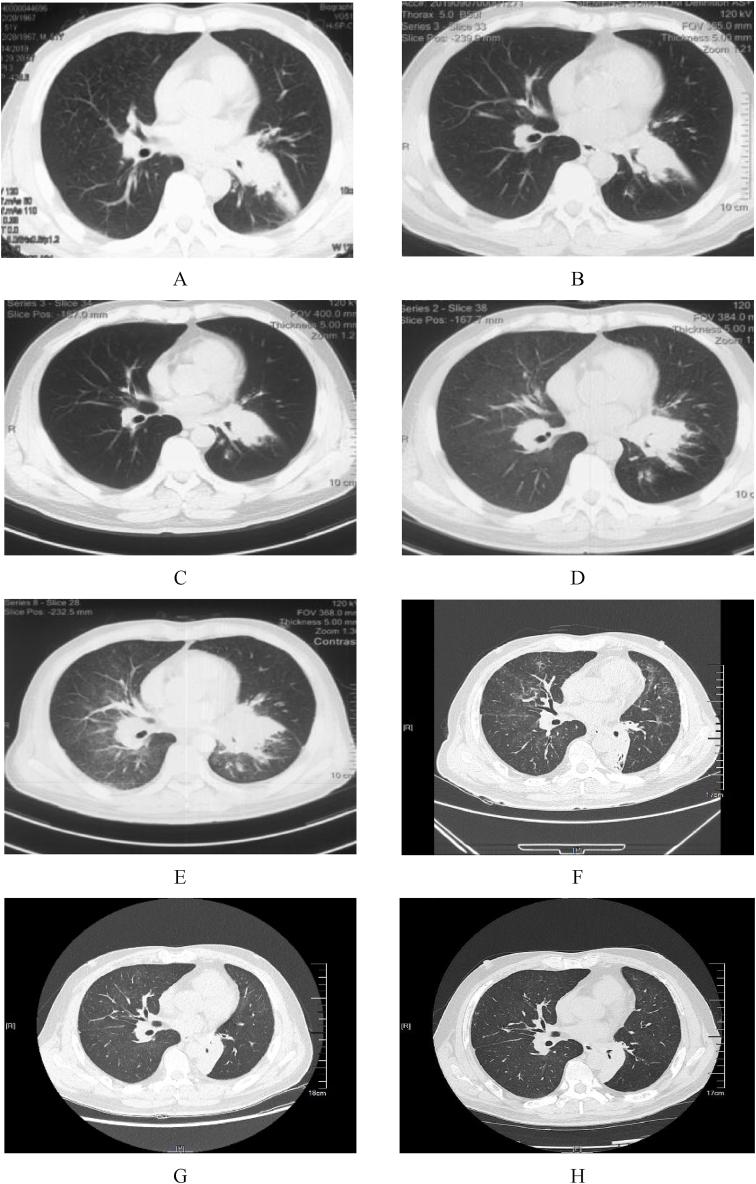

Leptomeningeal metastasis (LM) is one of the most serious complications of advanced non-small cell lung cancer (NSCLC) and lacks standard treatment. Patients with LM often have a poor prognosis. Here, we report a 51-year-old man diagnosed as advanced lung adenocarcinoma and gene sequencing indicated no sensitive driver gene mutation. Pemetrexed and cisplatin plus bevacizumab was administered as first-line therapy. He received pembrolizumab plus nab-paclitaxel as second-line therapy and developed neurological symptoms soon. Later, he was diagnosed LM by cerebrospinal fluid (CSF) cytology and gene sequencing of lung tissue rebiopsy demonstrated epidermal growth factor receptor (EGFR) sensitive mutation. The patient received high-dose (160mg) osimertinib therapy but still could not tolerate severe neurological symptoms and developed cardiac adverse event. After that, standard-dose (80mg) osimertinib plus anlotinib was administered and this treatment regimen resulted in the alleviation of neurological symptoms. As the recent follow up, the curative effect was evaluated stable disease (SD) and the patient gained a progression-free survival (PFS) of more than 15 months. We report this successful salvage therapy of osimertinib plus anlotinib in an advanced lung adenocarcinoma patient who developed LM after failure on previous treatment until EGFR mutation was confirmed through rebiopsy.

软脑膜转移(LM)是晚期非小细胞肺癌(NSCLC)最严重的并发症之一,且缺乏标准治疗方法。LM患者的预后通常较差。在此,我们报告一名51岁男性,被诊断为晚期肺腺癌,基因测序显示无敏感驱动基因突变。培美曲塞和顺铂联合贝伐单抗作为一线治疗方案。他接受帕博利珠单抗联合白蛋白结合型紫杉醇作为二线治疗,很快出现了神经症状。后来,通过脑脊液(CSF)细胞学检查诊断为LM,肺组织再次活检的基因测序显示表皮生长因子受体(EGFR)敏感突变。该患者接受了高剂量(160mg)奥希替尼治疗,但仍无法耐受严重的神经症状,并出现了心脏不良事件。此后,给予标准剂量(80mg)奥希替尼联合安罗替尼治疗,该治疗方案使神经症状得到缓解。作为近期随访,疗效评估为疾病稳定(SD),患者获得了超过15个月的无进展生存期(PFS)。我们报告了在一名晚期肺腺癌患者中奥希替尼联合安罗替尼的成功挽救治疗,该患者在先前治疗失败后发生LM,直至通过再次活检确认EGFR突变。